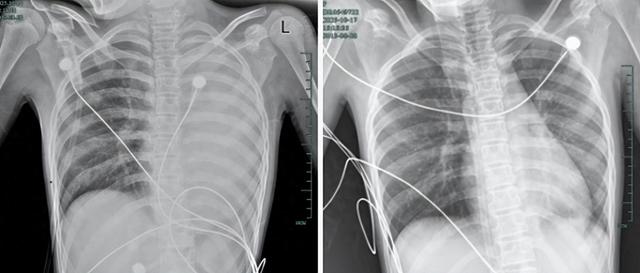

治疗前后影响对比,左肺从“白肺”到正常状态。

呼吸急促、胸闷胸痛,体温38.5℃,只能靠5L/min的面罩吸氧维持血氧,胸片显示左肺已完全呈“白肺”改变,肺部炎症进展迅猛。